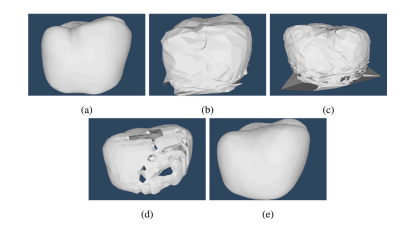

Fig. 3. (a) Dental arch with a prep, (b) generated context, (c) die (prepared tooth),(d) Ground truth crown, (e) extracted margin line.

图3:(a) 带有预备体的牙弓,(b) 生成的背景信息,(c) 代型(预备后的牙齿),(d) 真实的牙冠,(e) 提取出的边缘线。